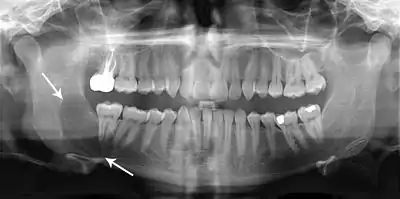

Radiographs of odontogenic keratocysts show well-defined radiolucent areas with rounded or scalloped margins which are well demarcated.[11] These areas can be multilocular or unilocular. The growth pattern of the lesion is very characteristic from which a diagnosis can be made as there is growth and spread both forward and backward along the medullary cavity with little expansion. No resorption of teeth or inferior dental canal and minimal displacement of teeth is seen. Due to lack of expansion of the odontogenic keratocyst, the lesion can be very large when radiographically discovered.[9]